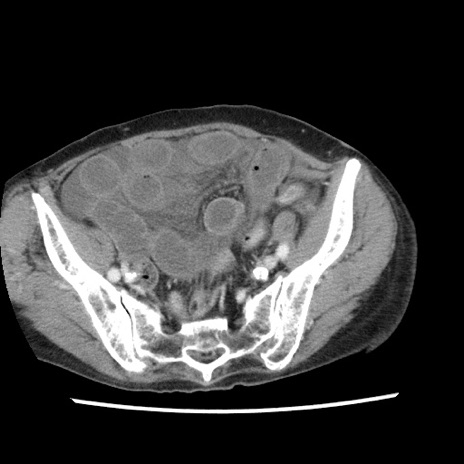

症例1(横断像)

【症例】80歳代女性

【主訴】腹痛

【現病歴】8時間前から腹痛あり来院。

【既往歴】糖尿病、脂質異常症、子宮体癌にて子宮全摘術

【身体所見】意識清明・会話良好だが腹痛で苦悶様、全腹部にわたって反跳痛と圧痛あり

【データ】WBC 13600、CRP 0.14、LDH 224、CK 90